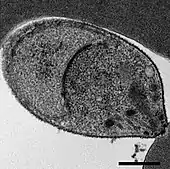

Malaria is traditionally diagnosed by examining Giemsa-stained blood films under a microscope; however, differentiating P. knowlesi from other Plasmodium species in this way is challenging due to their similar appearance.[11] P. knowlesi ring-stage parasites stained with Giemsa resemble P. falciparum ring stages, appearing as a circle with one or two dark dots of chromatin.[17] Older trophozoites appear more dispersed, forming a rectangular-shape spread across the host cell called a "band-form" that resembles the similar stage in P. malariae.[17] During this stage, dots sometimes appear across the host red blood cell, called "Sinton and Mulligans' stippling".[17] Schizonts appear, similarly to other Plasmodium species, as clusters of purple merozoites surrounding a central dark-colored pigment.[17]